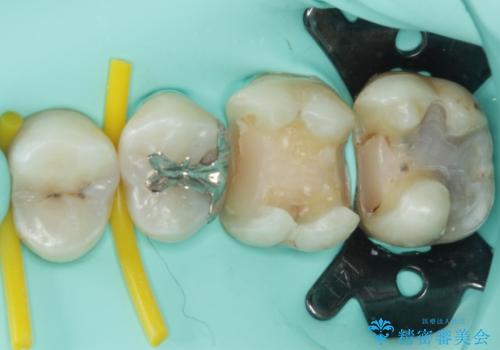

- 奥歯に頻繁に物が挟まるとのことで来院された患者様です。

最近ものが挟まりやすくなったり、冷たいものがしみるようになったりといった症状があり、診査したところ、むし歯や歯質の欠損、不適修復物などが認められました。

精度の高いセラミックインレーによる修復治療を行うこととしました。